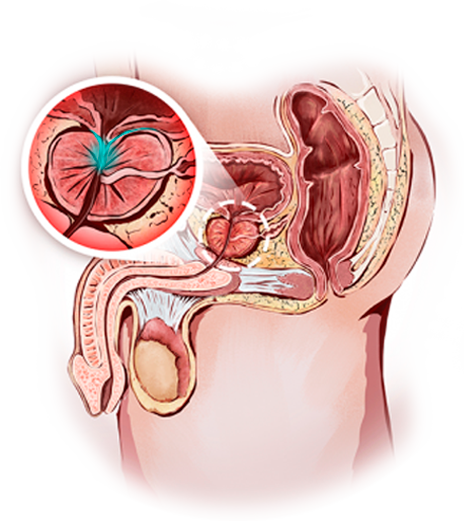

Tengo como compromiso mejorar la salud de nuestra comunidad y promover la prevención de patologías que afectan al aparato urinario, glándulas suprarrenales y retroperitoneo de ambos sexos, y el aparato reproductor masculino.

El Dr. Alejandro Palmeros Rodríguez es un médico especialista en urología comprometido con el bienestar de sus pacientes. Mediante su conocimiento y el uso de tecnología puede lograr la recuperación de distintos padecimientos y lograr una vida sana.